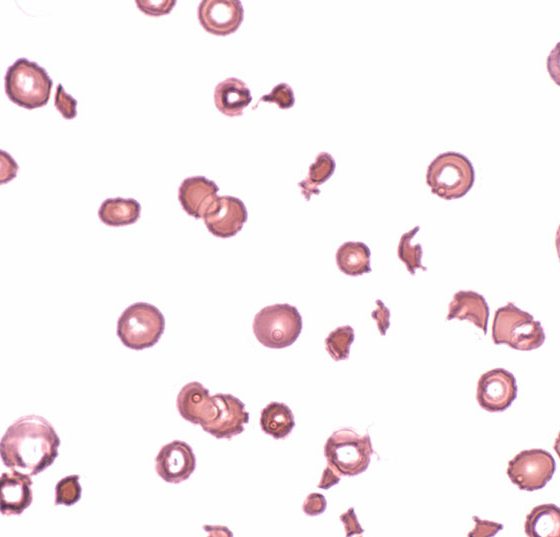

• Thrombozyten- und Leukozyten-Anomalien

Klonale oder reaktive Ursachen?

Das Ursachenspektrum von Blutbildveränderungen ist vielfältig. Eine Knochenmarkspunktion sollte bei Vorliegen von «Red Flags» niederschwellig erfolgen und wird beispielsweise zur Diagnosesicherung einer B-lymphoblastischen Leukämie (B-ALL) durchgeführt. Auch bei Thrombozytopenie ist...…

ttp_blutbild